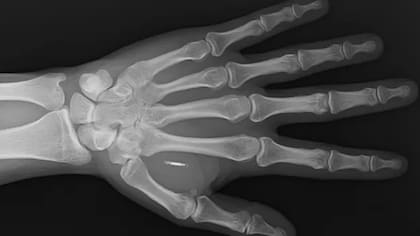

El chip de Walletmor, que pesa menos de un gramo y es un poco más grande que un grano de arroz, está compuesto de un pequeño microchip y una antena recubierta de un biopolímero, un material de origen natural, similar al plástico.

Paprota agrega que es completamente seguro, tiene los permisos necesarios, funciona inmediatamente después de ser implantado y se mantendrá en su lugar sin moverse. Tampoco requiere una batería u otra fuente de energía. La firma dice que vendió más de 500 chips.

La tecnología que utiliza Walletmor es la NFC (Near-Field Communication, conexión de proximidad), el sistema de pago sin contacto en los teléfonos inteligentes. Otros implantes de pago se basan en la identificación por radiofrecuencia (RFID), que es la tecnología que normalmente se encuentra en las tarjetas físicas de débito y crédito sin contacto.